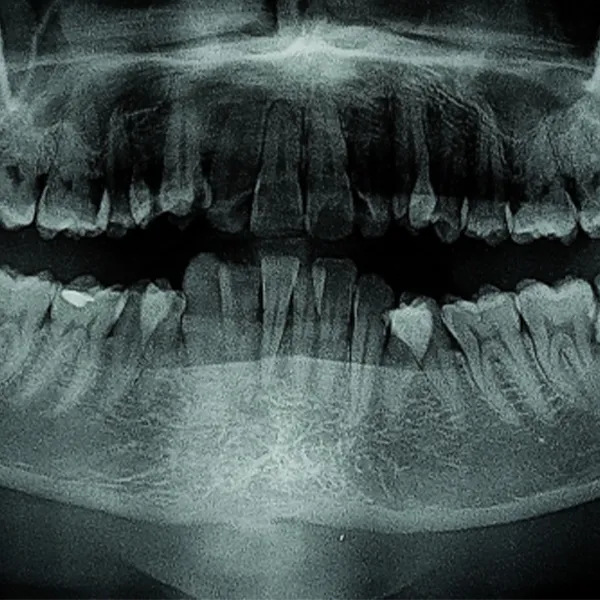

Konsultacija ir diagnostika

Atliekamas išsamus burnos ertmės ištyrimas, rentgeno arba 3D tomografijos tyrimai,

sudaromas gydymo planas.